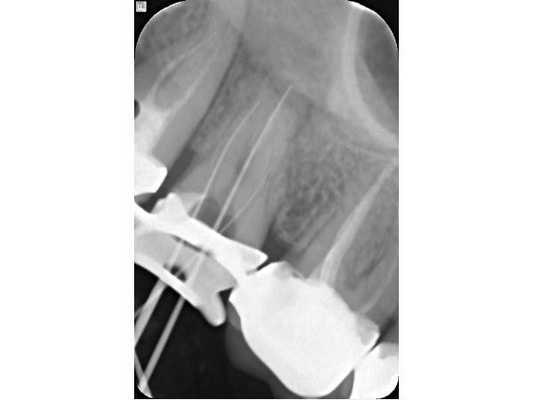

- Врач-ортопед отсепарировал (отделил) 17 зуб от соседних и снял постоянную ортопедическую конструкцию. Изоляция произведена системой коффердам (пластиной из латекста).

- После снятия пломбы — некрэктомия (удаление нежизнеспособных тканей), восстановление стенки для проведения эндодонтического лечения (лечения корневых каналов).

- Дезобтурация (удаление старой пломбы) корневых каналов, заполненных резорцин-формалиновым цементом.

- Обработка каналов эндодонтическим инструментом Profile: 40.04 (размер 40, конусность 0,4) — щёчные каналы, 45.04 (размер 45, конусность 0,4) — нёбный канал.

- Медикаментозная обработка гипохлоритом натрия 3 %, ЭДТА 18 %, активация растворов.

- Обтурация (пломбирование) гидроокисью кальция на 3 недели. Антибиотики не назначались.